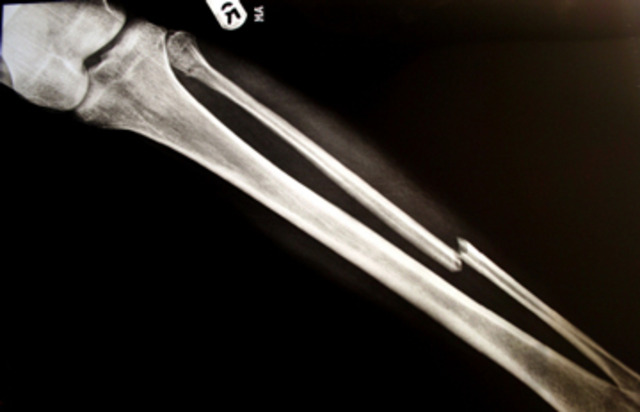

• My firsy major injury.

My firsy major injury.

I was playing in a rec. soccer game and broke my left tibia. I was running down the field with players kicking the ball behind me. While I was running, the ball went under my left foot. When I stepped down, I stepped on the ball and broke my leg.

• I re-brake my left leg

I re-brake my left leg

I re-brake my left leg in the same spot as before. It was only a couple months after the firts broken leg when I slipped on ice and re-broke my leg in the exact same spot.